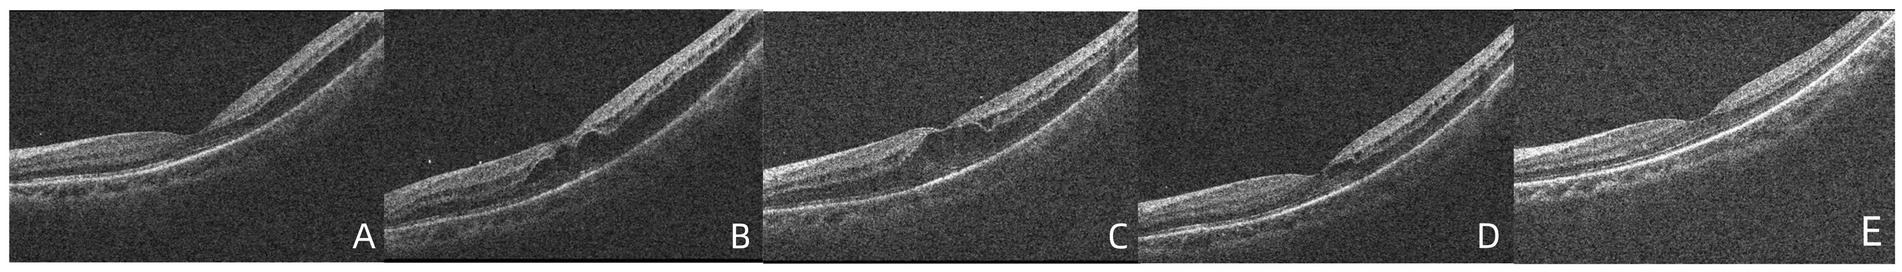

At the time of the patient’s visit, the axial length was 25.33 mm in the right eye and 25.16 mm in the left eye; his axial length 1 month ago was 25.24 mm in the right eye and 25.14 mm in the left eye. There was no significant difference in axial length between them. The corneal curvatures of the right and left eyes were 44.00 and 43.25 D, respectively. Anterior segment examination was normal, and no inflammatory cells were observed in the anterior chamber or vitreous of the left eye. B-ultrasonography revealed no vitreoretinal traction. Optical coherence tomography (OCT) demonstrated retinal splitting in the macular area, on the temporal side of the macula, and near the superior and inferior vascular arches, occurring in the outer plexiform layer without a macular hole, VMT, or macular epiretinal membrane (ERM) (Figure 1). Fluorescein and indocyanine green angiography revealed no capillary leakage in the macula or optic disc (Figure 2). There were no obvious abnormalities in the binocular visual field. Although no active inflammation was present in the left eye, the patient was given empirical therapy including oral prednisolone at 60 mg/day for 1 week, followed by 50 mg/day for 1 week. Steroid eye drops were prescribed as well. After this 2-week treatment, OCT showed that the retinoschisis had become aggravated, and the best-corrected visual acuity had decreased to 20/66 (Figures 3A,B and Figures 4A,B,E,F,I,J).

Figure 3. (A,B) OCT demonstrated that foveoschisis was aggravated 2 weeks after the patient was diagnosed and the foveoschisis cavity was expanded, and the best-corrected visual acuity (BCVA) decreased to 20/66. (C) Twenty-seven days after diagnosis, the OCT demonstrated that there was no obvious improvement in foveoschisis. (D) Forty days after diagnosis, the foveoschisis began to improve significantly; the volume of the cavity was significantly reduced. (E) Fifty-five days after diagnosis, the retinoschisis in the macula had resolved completely in the OCT appearance, with BCVA recovering to 20/33.

The patient visited our hospital again after returning from Beijing (27 days after diagnosis). OCT demonstrated that there was no obvious improvement in the foveoschisis (Figure 3C); however, the retinoschisis near the inferior (Figure 4C), superior (Figure 4G) vascular arches and the temporal of macula (Figure 4K) had begun to improve. The prednisolone was reduced to 30 mg/day and then reduced by 10 mg every 3 days. Forty days after diagnosis, the foveoschisis began to markedly improve (Figure 3D), and the retinoschisis near the inferior (Figure 4D) and superior (Figure 4H)vascular arches and the temporal side of the macula (Figure 4L) had completely resolved. Fifty-five days after diagnosis, OCT showed that the retinoschisis in the macular region had also completely resolved, with the best-corrected visual acuity recovering to 20/33 (Figure 3E). After a follow-up observation of 14 months, the vision of his left eye was stable, and macular OCT indicated that the structure of each layer of the retina was normal.

Figure 4. (A–D) OCT demonstrated that no significant improvement in retinoschisis near the inferior vascular arch 2 weeks after diagnosis, 27 days after diagnosis, the retinoschisis cavity was reduced, 40 days after diagnosis, the retinoschisis had completely resolved. (E–H) OCT demonstrated that no significant improvement in retinoschisis near the superior vascular arch 2 weeks after diagnosis, 27 days after diagnosis, the retinoschisis cavity was reduced, 40 days after diagnosis, the retinoschisis had completely resolved. (I–L) OCT demonstrated that no significant improvement in retinoschisis near the temporal side of the macula 2 weeks after diagnosis, 27 days after diagnosis, the retinoschisis cavity was reduced, 40 days after diagnosis, the retinoschisis had completely resolved.